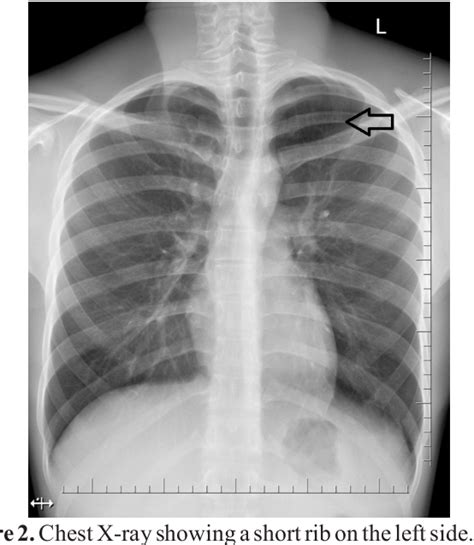

Eric McAllister Blog